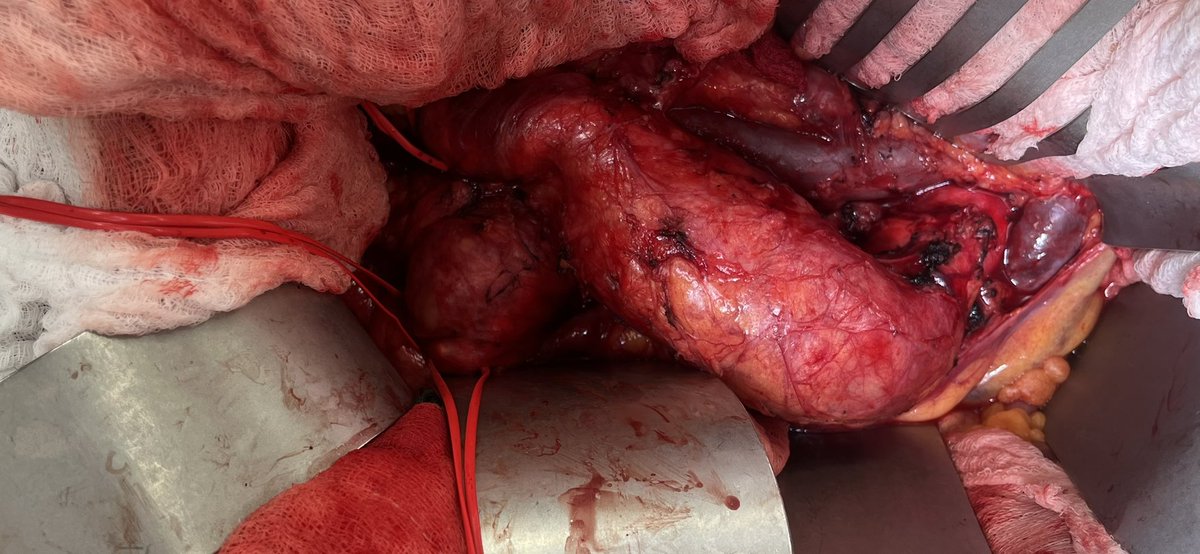

Open aortic surgery alive and well at @MCWVascSurg. Aortoiliac aneurysms with prior Type A dissection extending to iliacs. Aorto-R EIA (internal had aneurysm so ligated)-L IIA with jump to EIA.